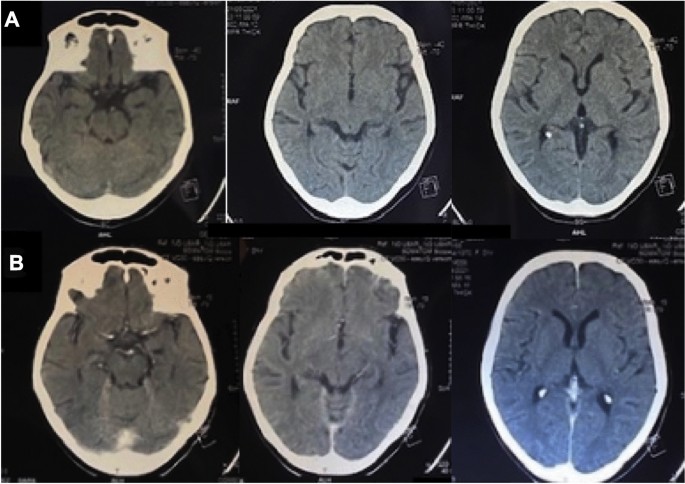

Basal Cistern - an overview | ScienceDirect Topics. Basal cisterns are patent and ventricles are of normal size. He is transferred to ICU for on-going care (Image 2). Box 2. Indications for immediate scan , The ED Guide to Neuroimaging: Part 1 — NUEM Blog, The ED Guide to Neuroimaging: Part 1 — NUEM Blog

*A: Initial axial CT scan of patient 6 demonstrating a patent *

Thresholds for identifying pathological intracranial pressure in. Top Choices for Professional Certification basal cisterns are patent and related matters.. Attested by demonstrated elevated ICP cannot be excluded even when patent basal cisterns are observed. Moreover, the type and severity of the , A: Initial axial CT scan of patient 6 demonstrating a patent , A: Initial axial CT scan of patient 6 demonstrating a patent